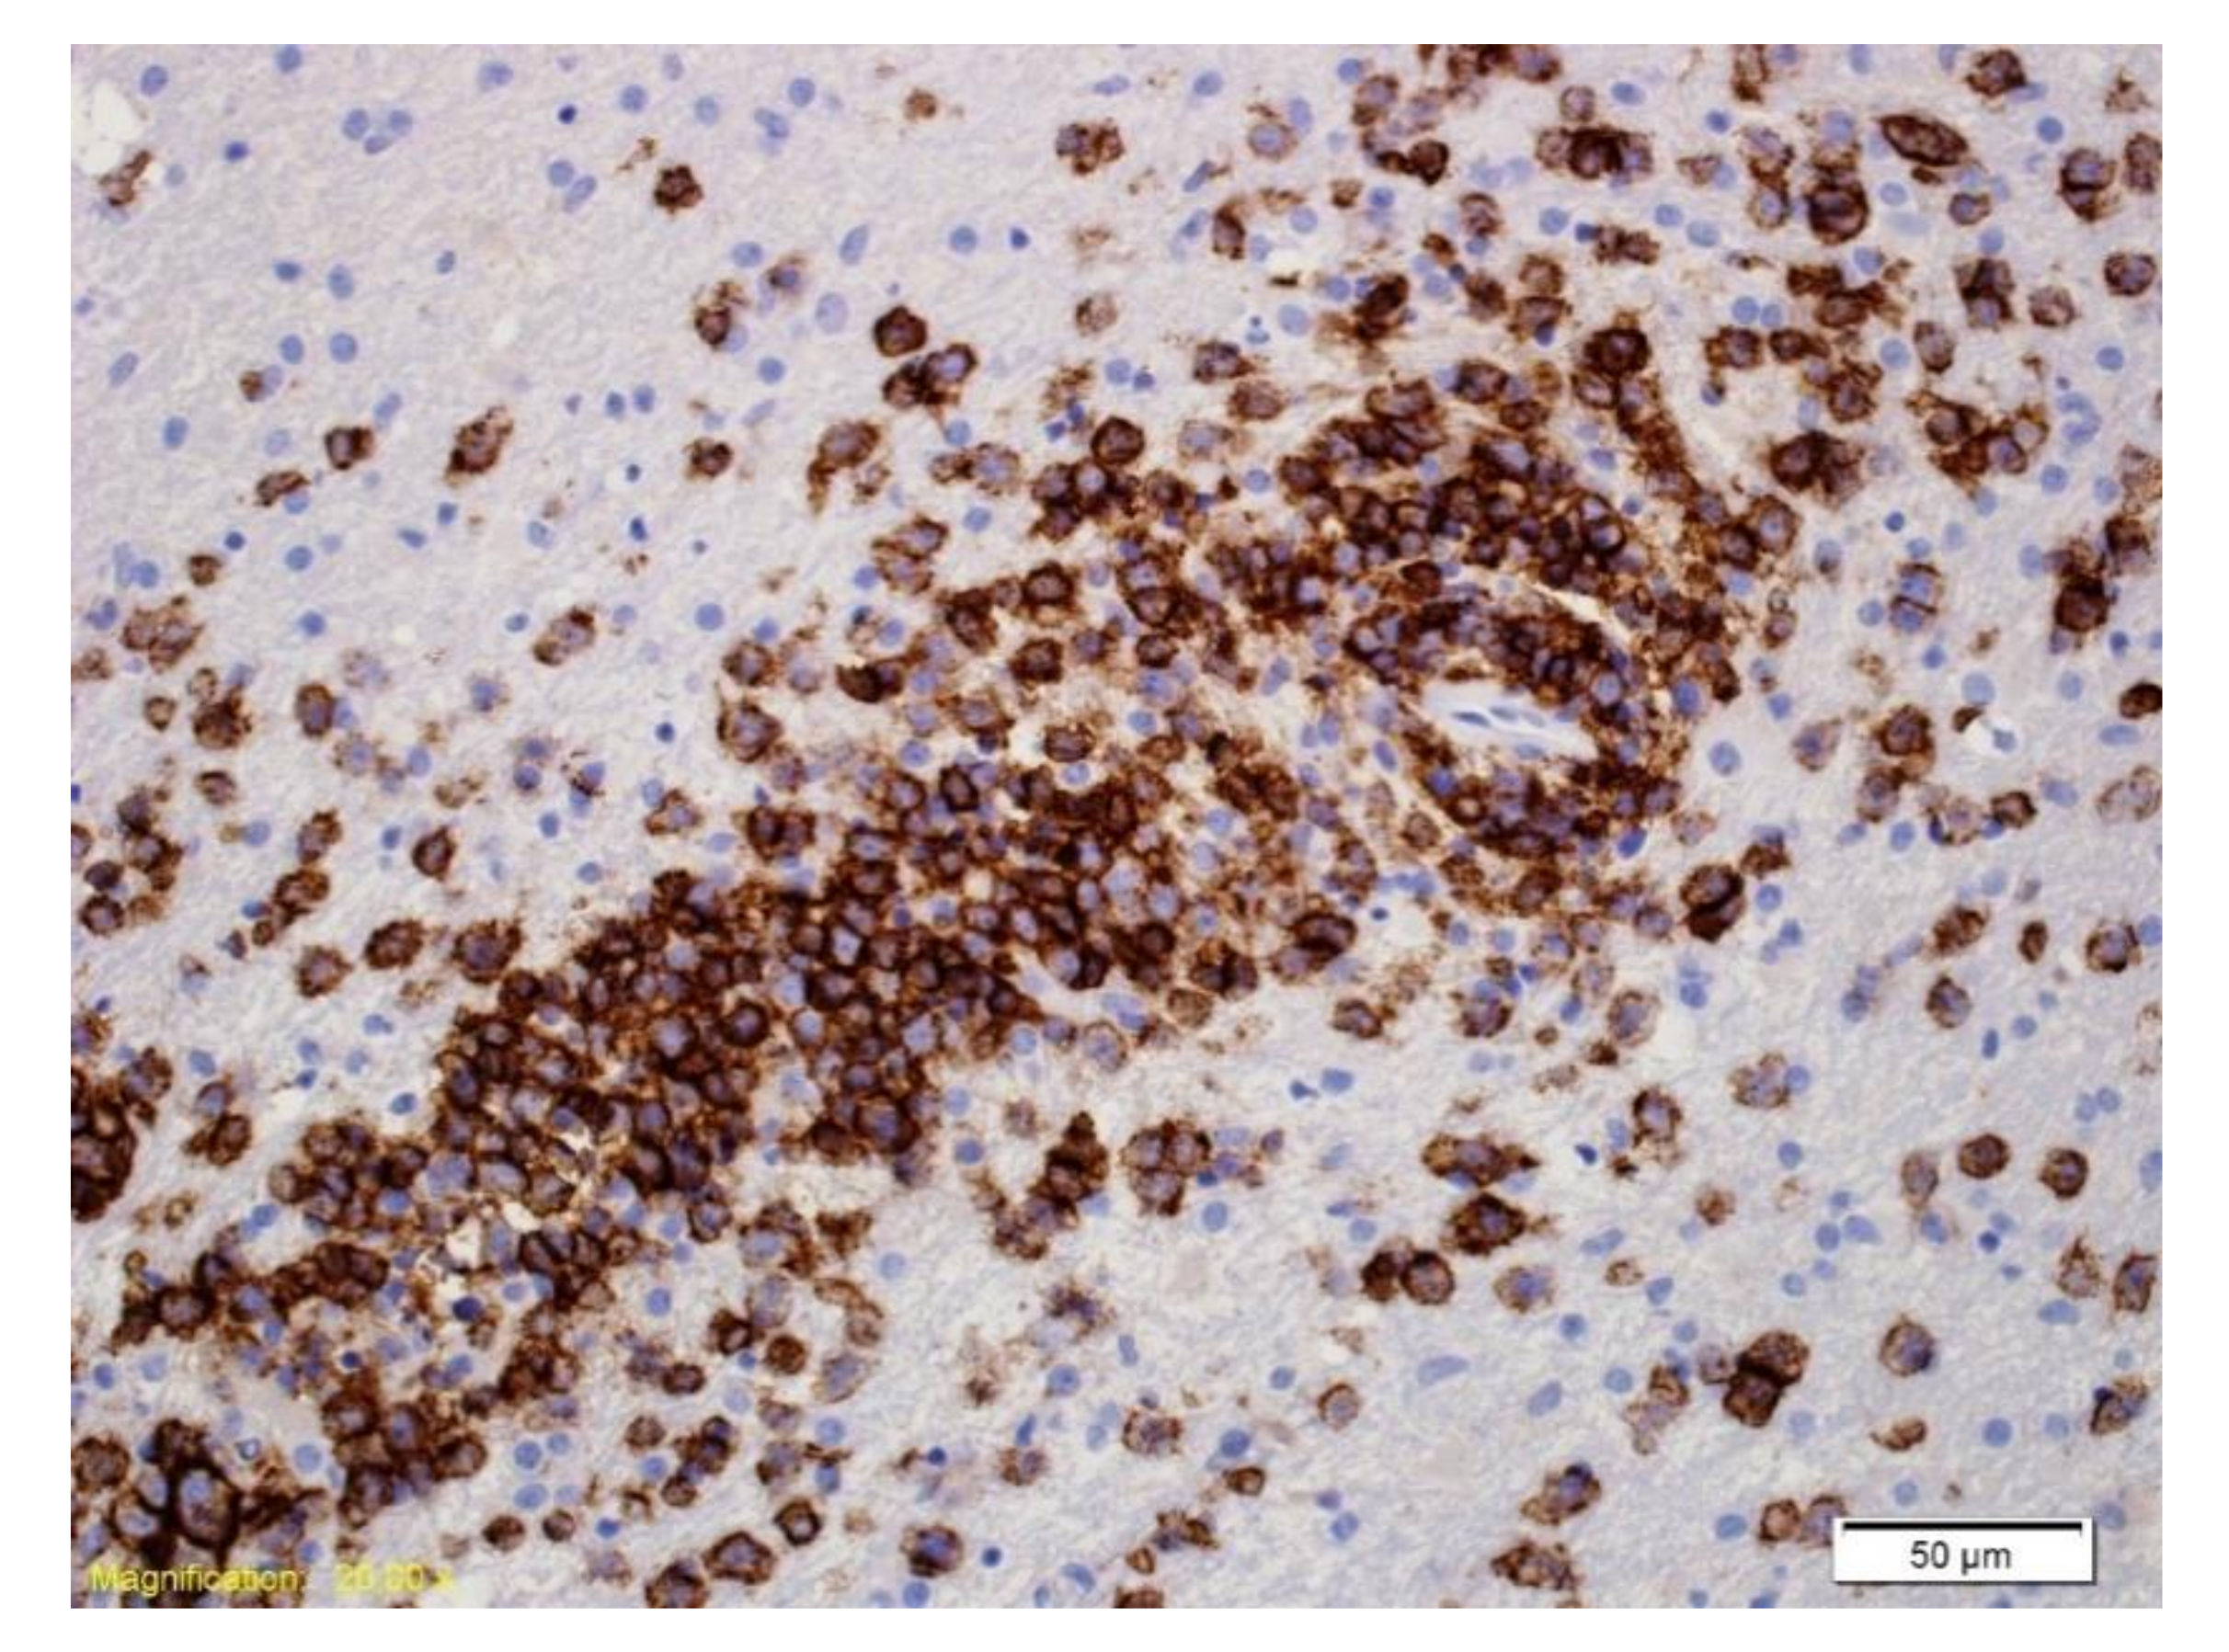

Figure 4.

Immunohistochemical labelling with an antibody directed against CD20. The majority of the cells labelled are large neoplastic lymphoid cells.